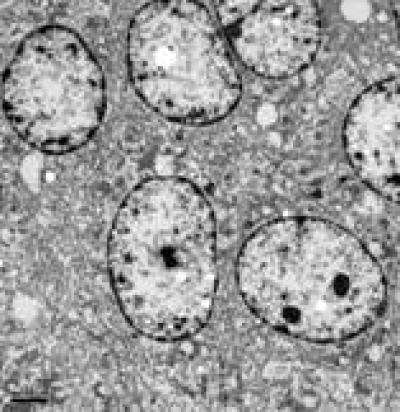

After pretreatment with 5-hydroxymethylfurfural, some mitochondria were swollen, but morphology was mostly normal in H2O2-injured rat hippocampal neurons (transmission electron microscope, × 4 000).

(Photo Credit: Neural Regeneration Research)